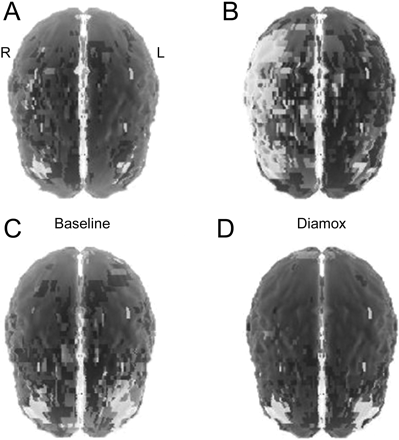

与乙酰唑胺显示减少灌注SPECT扫描大脑半球,更糟糕的是在右边,符合减少血管储备MCA领土(图3)。神经心理评估(提供了额外程度的敏感性的检测脑功能障碍)强烈建议赤字在右半球功能(受损的视觉空间的判断,构造失用症,减少了洞察力和自我监控),没有证据表明impersistence(电动机或其他)。他的视觉感知能力下降的受损范围和他的复制复杂的数字是明显的遗漏的元素以及不准确。他缓慢时获取口头信息在列表格式和回忆只有5 10项,尽管多个试验。有证据的执行功能障碍与缺陷时钟画(号码重复,手不正确)。没有任何证据表明焦虑或抑郁。这些孤立的赤字在学习和记忆、执行功能、和视觉空间功能符合减少灌注脑结构提供的MCA,包括颞叶。

SPECT扫描(A, B)和乙酰唑胺(C, D)显示减少灌注的脑半球,更糟糕的是在右边,符合减少大脑中动脉的血管储备地区(A, B) prestent,返回的脑血流量储备植入支架后的(C, D)。

病人现在已经进步灌注不足的症状,可参考的症状性颅内狭窄,尽管最佳医疗管理,介入管理被认为是。病人接受的翼展self-expandable支架放置正确的MCA (图2C) 2周后SPECT和认知测试。乙酰唑胺脑SPECT重复3天poststent显示改善皮质灌注没有受损的血管储备的新领域图3B)。4周后,重复神经心理测试显示完整的认知功能(平均或更好),包括正常的视觉空间技能,语言学习、记忆和执行功能,除了轻微的缺陷与受益于复杂的视觉记忆检索识别信号。这种患者的颅内疾病的潜在病因仍然不明。